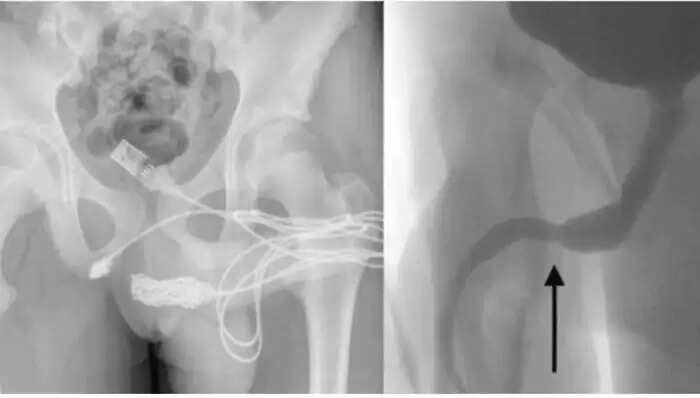

Doctors had to perform surgery to remove the USB cable from his private area. After making a significant incision near the penis, they successfully extracted the cable. A CT scan revealed the cable lodged inside, leaving the medical team with no option but to proceed with the operation. Following a successful surgery, the doctors informed that the young man was discharged without any internal injuries, although he would need to return for a follow-up scan in two weeks.